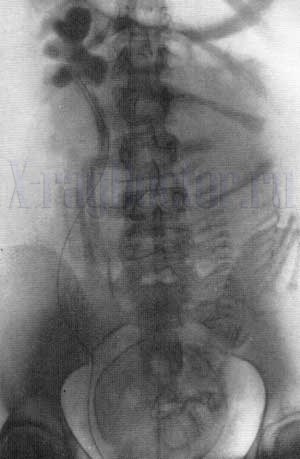

На снимке в норме мочевой пузырь характеризуется следующими показателями:

- пирамидальная или продолговатая форма;

- овальные или округлые контуры.

Как выглядит мочеполовая система на рентгене у женщин, мужчин и детей:

- У женщин форма пузыря овальная. Его поперечный размер больше продольного. На цистограмме визуализируется вогнутость внешнего контура.

- У детей орган имеет грушевидную форму. Он обращен суженной частью к лобковым костям. Физиологически тень пузыря располагается на уровне лобкового симфиза.

При цистографии с жидким контрастом четко прослеживаются опухоли малого таза (аденома, конкременты, дивертикулы). На аксиальной рентгенограмме у мужчин при этом прослеживается треугольная форма органа. Мешковидные выпячивания при этом выглядят как участки просветления на фоне интенсивной металлической тени.